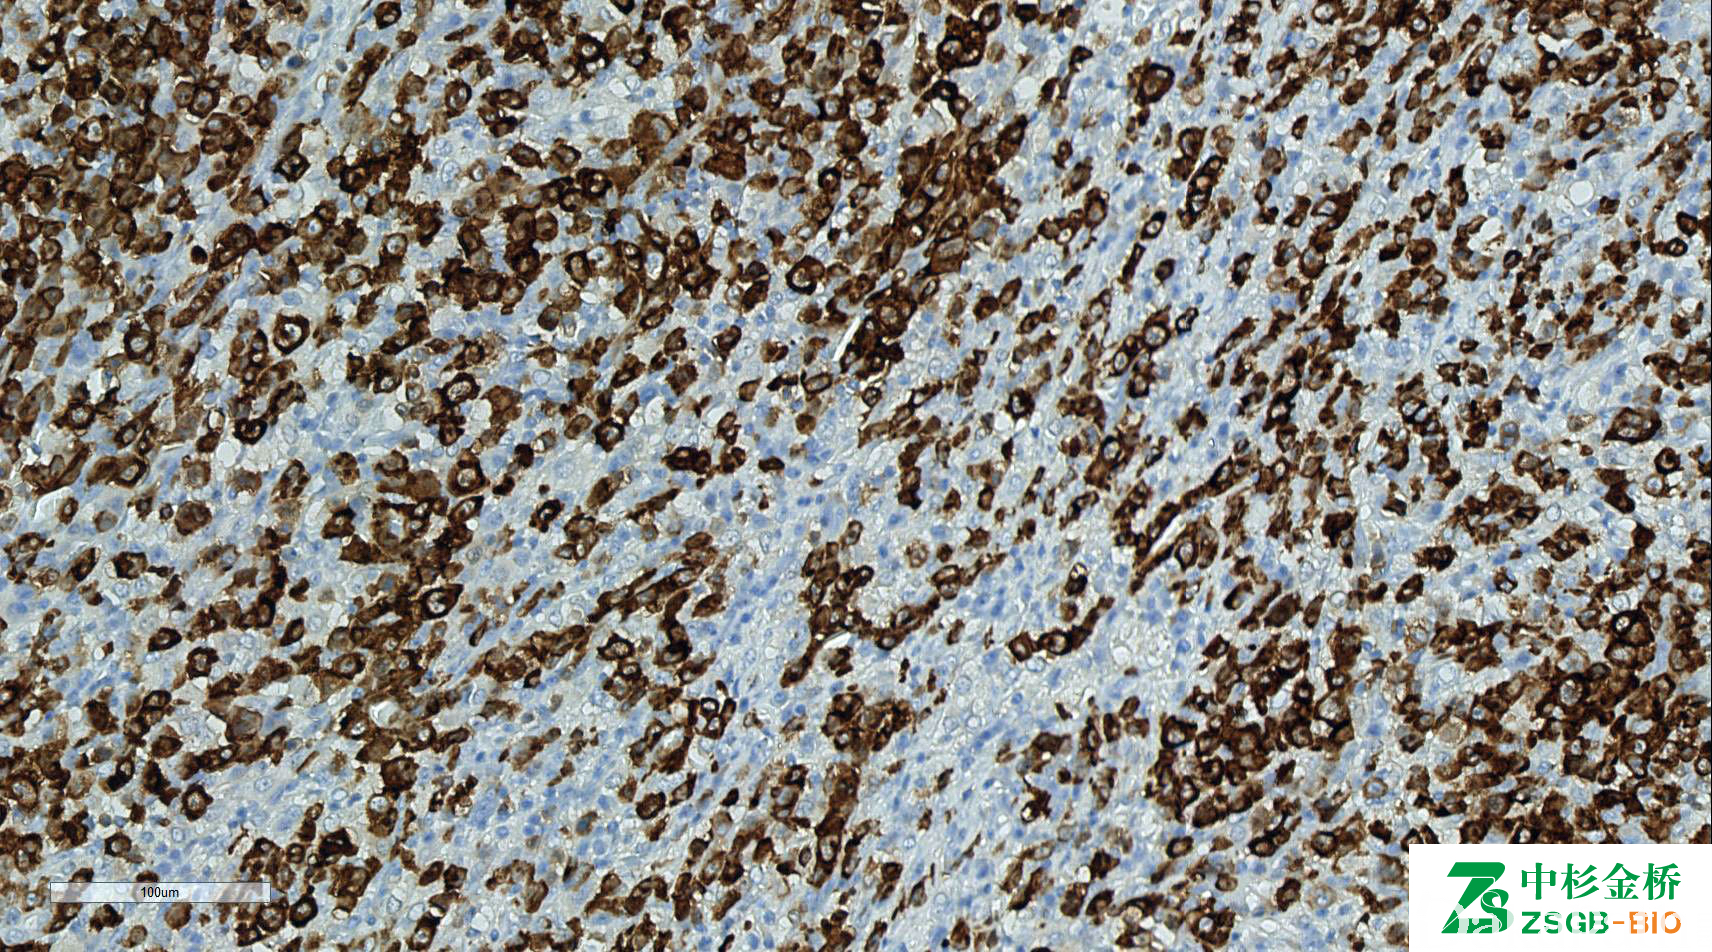

CD30

淋巴细胞活化基因。标记大细胞间变性淋巴瘤,何杰金病 R-S 细胞,活化的 T、 B 细胞。胞膜和胞质阳性常见于淋巴造血系统肿瘤,包括 HL、ALCL 及部分大细胞淋巴瘤;弥漫阳性常见于非淋巴造血系统肿瘤,如胰腺癌、鼻咽癌、未分化癌及恶黑等。还可表达于生殖细胞性肿瘤,如胚胎性癌。

信号定位: 胞膜、胞质(高尔基区)、弥漫型